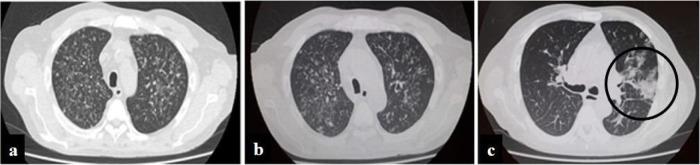

We report a case of disseminated histoplasmosis and COVID-19 infection in a renal transplant recipient in Argentina. The patient exhibited respiratory symptoms, and a chest computed tomography scan (CT) showed multiple bilateral centrilobular opacities with a tree-in-bud pattern in both lobes. The patient was initially treated as having bacterial community-acquired pneumonia, and then tuberculosis. A month later, histoplasmosis was diagnosed, and Histoplasma capsulatum LAmB clade was isolated from sputum, skin and oral lesions. The patient was hospitalized and treatment was started with intravenous liposomal amphotericin B. During the course of the antifungal therapy the respiratory symptoms worsened, a new chest CT showed a unilateral lesion with a ground glass appearance and SARS-CoV-2 was detected in a new nasopharyngeal sample. In addition, plasma therapy was administered, and the immunosuppressive regimen was adjusted (everolimus was interrupted, mycophenolate mofetil reduced, and meprednisone increased). Finally, the patient's progress was favorable and was discharged after five days on oral itraconazole treatment for histoplasmosis.

我们报告了一例在阿根廷的肾移植受者中发生的播散性组织胞浆菌病和 COVID-19 感染。该患者表现出呼吸道症状,胸部计算机断层扫描(CT)显示双侧多个小叶中心性混浊,呈树芽征。该患者最初被诊断为细菌性社区获得性肺炎,然后是肺结核。一个月后,诊断为组织胞浆菌病,从痰液、皮肤和口腔病变中分离出荚膜组织胞浆菌 LamB 枝。患者住院,并开始接受静脉注射两性霉素 B 脂质体治疗。在抗真菌治疗过程中,呼吸症状恶化,新的胸部 CT 显示单侧病变,呈磨玻璃样外观,新的鼻咽样本中检测到 SARS-CoV-2。此外,还进行了血浆治疗,并调整了免疫抑制方案(中断依维莫司,减少霉酚酸酯,增加泼尼松龙)。最后,患者的病情好转,在口服伊曲康唑治疗组织胞浆菌病五天后出院。